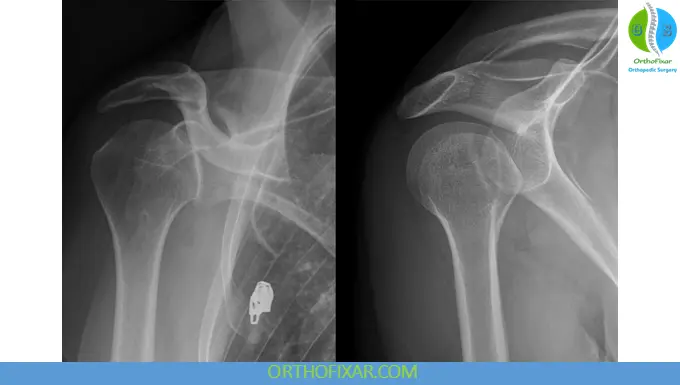

Key Radiographic Signs (AP View)

• Loss of normal humeral head–glenoid overlap

• Vacant glenoid sign (>6 mm space)

• Trough sign (reverse Hill-Sachs lesion; seen in ~75%)

• Internal rotation appearance (“light bulb sign”)

• Loss of humeral neck profile

Posterior Shoulder Dislocations xray